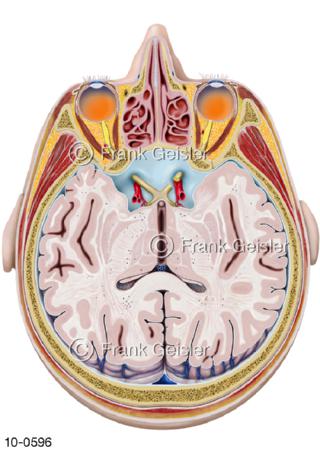

Bildergalerie Nervensystem

Bilder zum Nervensystem,dem Gehirn, Teil des zentralen Nervensystem, Zentralnervensystem ZNSmit Rückenmark, Abbildungen zum Nervengeflecht (Nervenplexus), die Verflechtungen von Nervenfasern, aus der Wirbelsäule hervortretende Nervenäst sowie Nervenzellen der Nerven